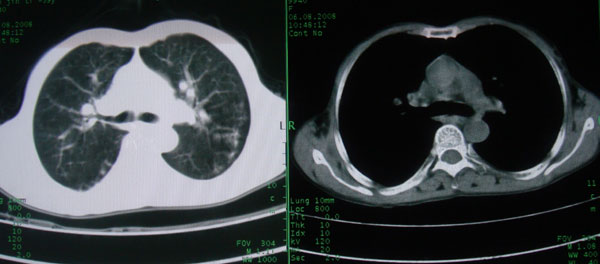

标题: CT15046:F59Y,咳嗽间断咳血丝痰就诊. [打印本页]

标题: CT15046:F59Y,咳嗽间断咳血丝痰就诊.

咳嗽\间断咳血丝痰就诊.